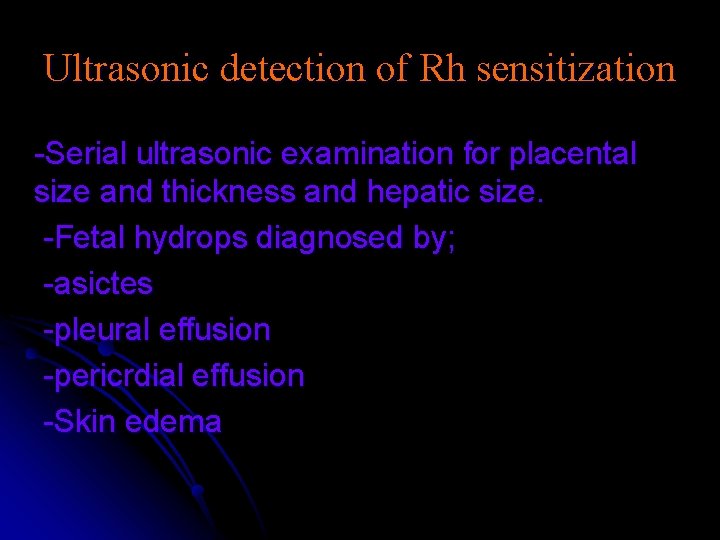

Ultrasonic detection of Rh sensitization -Serial ultrasonic examination for placental size and thickness and hepatic size. -Fetal hydrops diagnosed by; -asictes -pleural effusion -pericrdial effusion -Skin edema